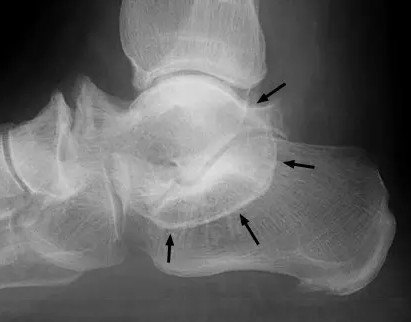

本征象用于描述跟骨距骨桥(或称跟距融合)的平片侧位表现,正位表现为